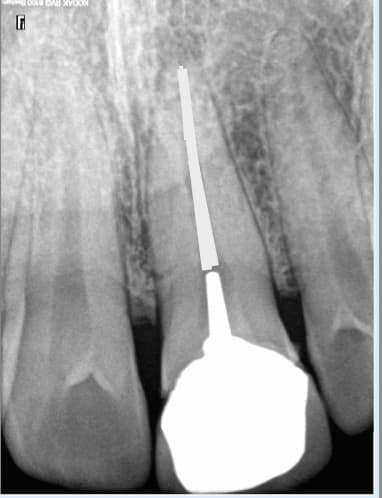

cette 21 est conforme aux recommandations radiologiquement ?

Et toutes les couronnes acceptées à l'epoque des DEP sur des endos foireuses étaient conformes radiologiquement ?

Qu'est ce que tu appelles conforme radiologiquement ? Le fait de ne pas avoir de pèche à l'apex le jour de la réalisation de l'endo ? -)

Dites moi dans votre consultation là. Mais il manque les radios recommandées par la HAS.

Examen incomplet : Indu. -)

Tu peux mettre la radio en fichier téléchargeable que je te fasse l’endos sur cette dent. Voir, tant qu'on y est, je traite en même temps la lésion apicale.

J'ai fait le RTE. mais je n'ai pas la technique pour traiter la lésion. Faut que je me forme. -)

Pour etre complet il faudrait refaire la couronne aussi. -)